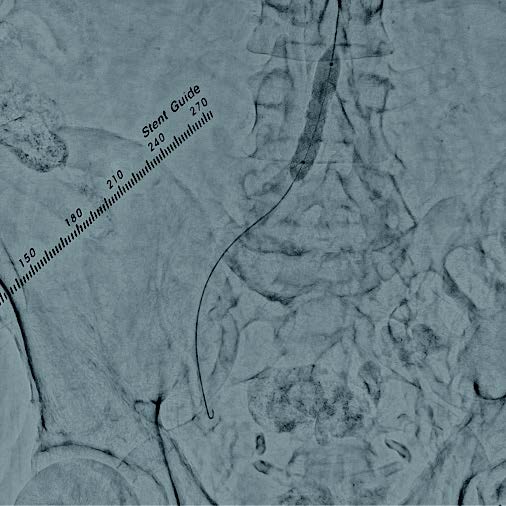

本症例は総大腿動脈からの順行性穿刺による右膝下動脈の治療を予定していることから、上腕動脈穿刺による腸骨動脈へのEVTを計画した。右上腕動脈から6 Frガイディングシースを用いてアプローチし、術前の下肢血管造影を行った。重症下肢虚血患者であり、安定したinflowの確保が重要と考え、高度石灰化を伴うことおよび血管径が11 mmと大きいことを踏まえ、後拡張の汎用性の高いVBX ステントグラフトを選択する方針とした。0.014 inchガイドワイヤーで病変通過後、6.0 × 40 mmバルーンで前拡張を行った(図1)。ガイドワイヤーを0.035 inchスティッフタイプに変更し、VBX ステントグラフト7 × 39 mmを後拡張での短縮を考慮し、数 mm 程度大動脈に突出させる形で留置した(図 2)。10.0 × 40 mmバルーンで後拡張(図3)を行い、IVUSで解離等がないことを確認し、最終造影で合併症が無いことを確認し手技を終了した。